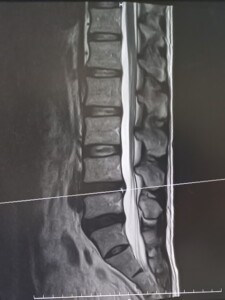

背骨と背骨の間にある「椎間板」は、衝撃を和らげるクッションの役割を担っています。

しかし、この椎間板が何らかの要因で後方に飛び出し、神経を圧迫してしまうと、腰やお尻・脚にかけて痛みやしびれを引き起こします。これが「椎間板ヘルニア」です。